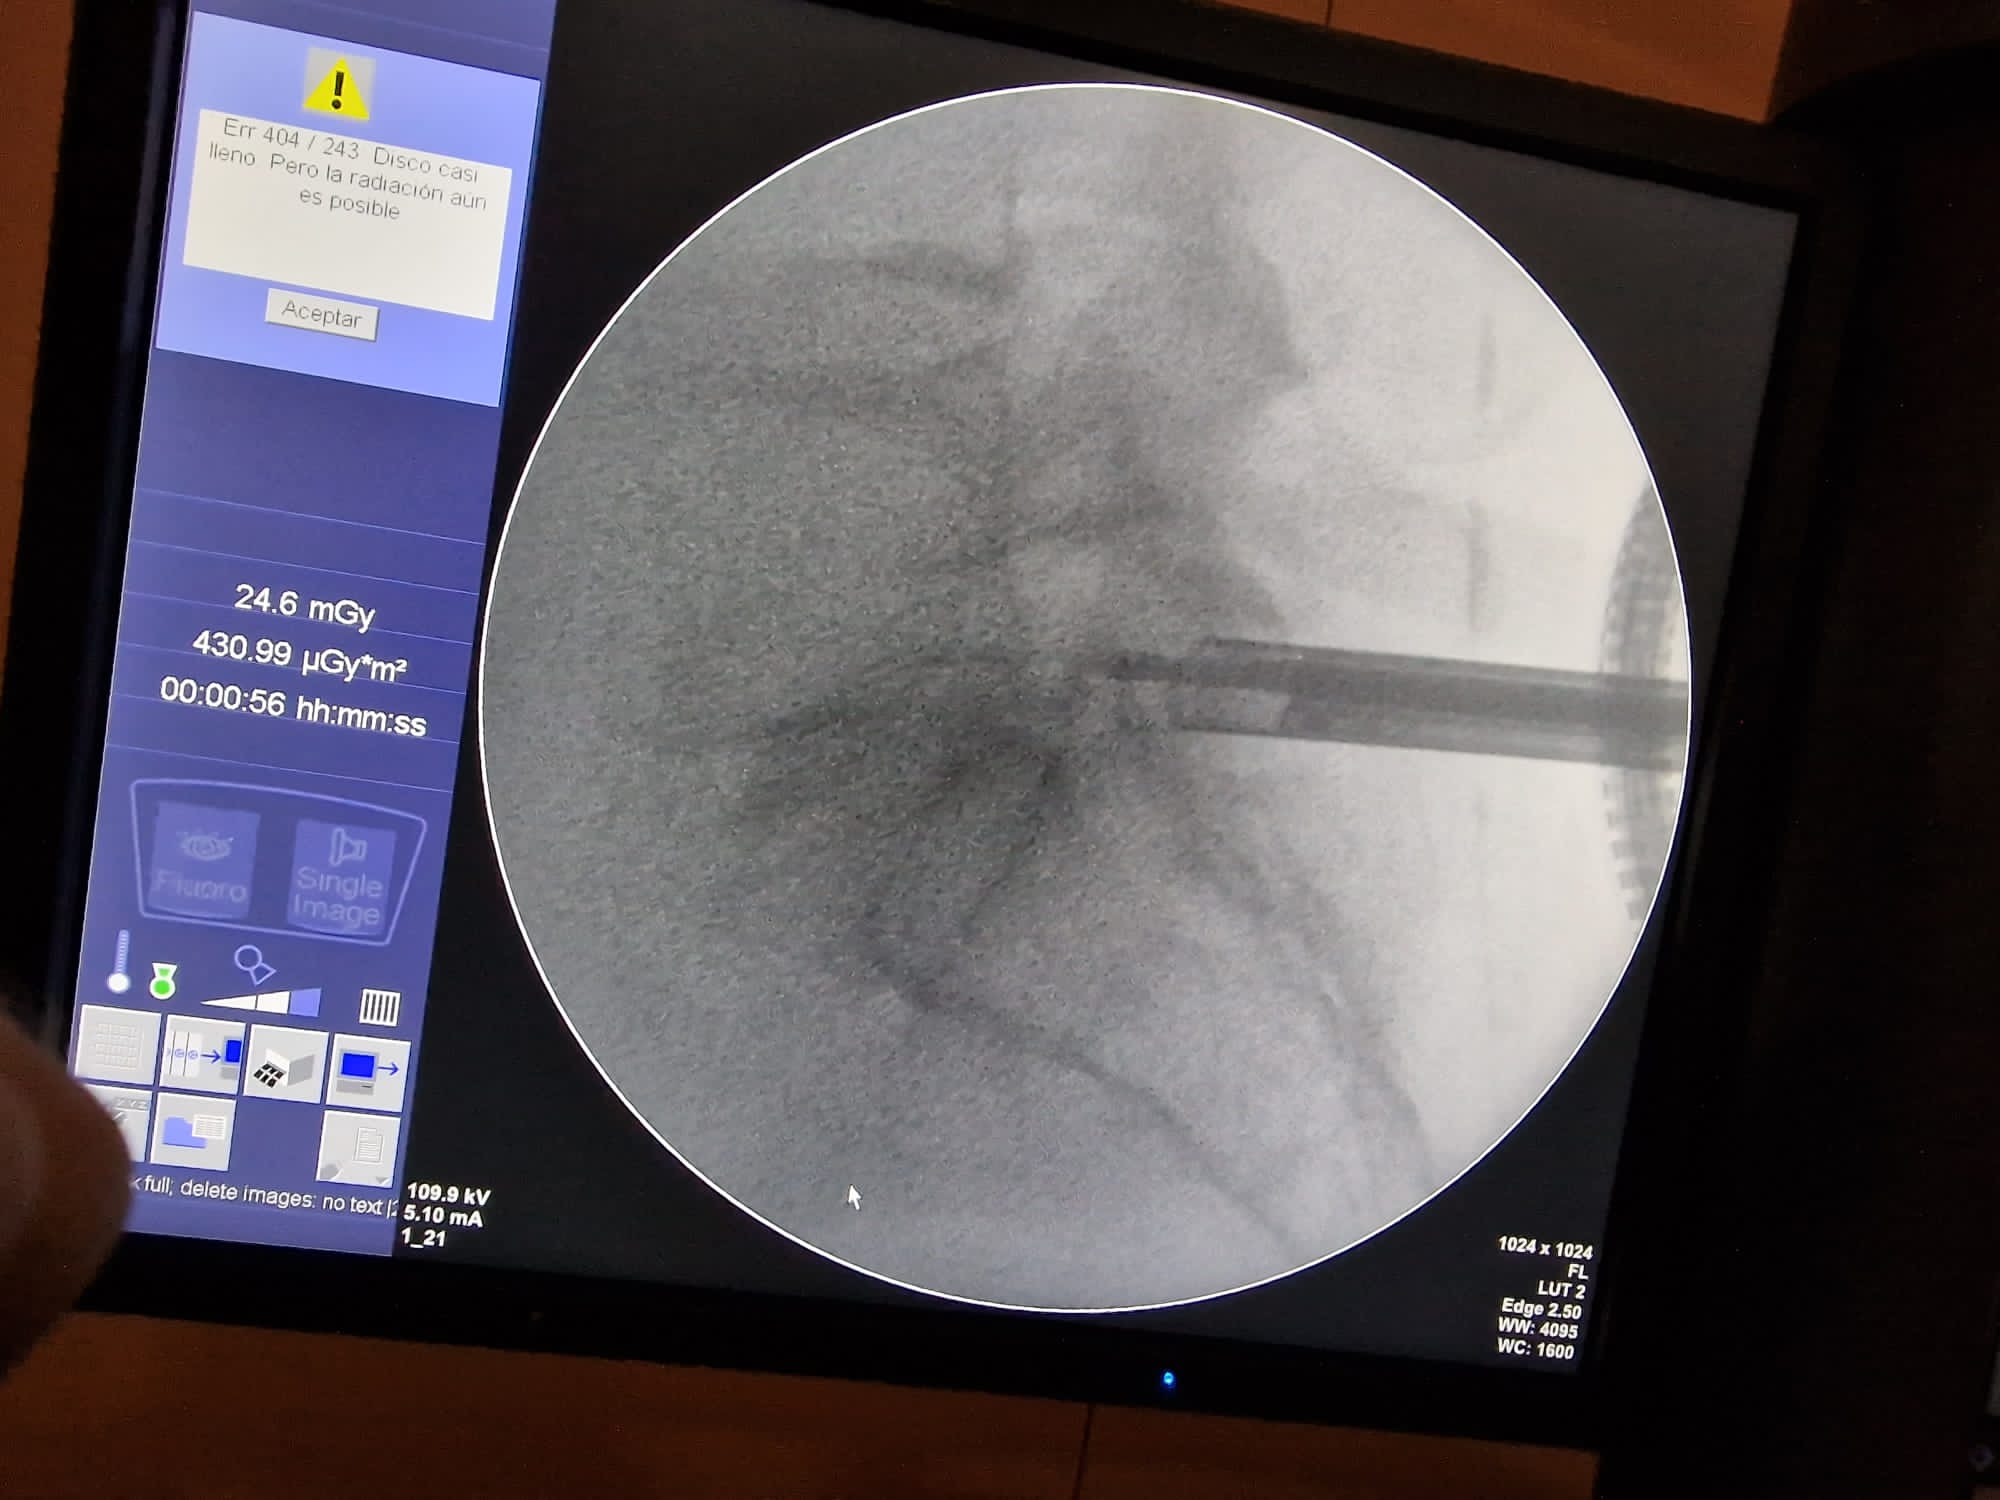

• Disectomía endoscópica

Disectomía endoscópica

• Discectomía Endoscópica

En la discectomía endoscópica, se realiza una pequeña incisión por la que se introduce un endoscopio (un tubo delgado con una cámara y luz) para visualizar y remover el material del disco herniado. Este método permite al cirujano trabajar con precisión y minimizar el daño a los tejidos circundantes.

Se trata de una técnica mini-invasiva de cirugía de columna en la que el acceso es a través de una única incisión por la que se introduce el set de trabajo endoscopico que consta de cámara, luz, irrigación y cánula de trabajo.